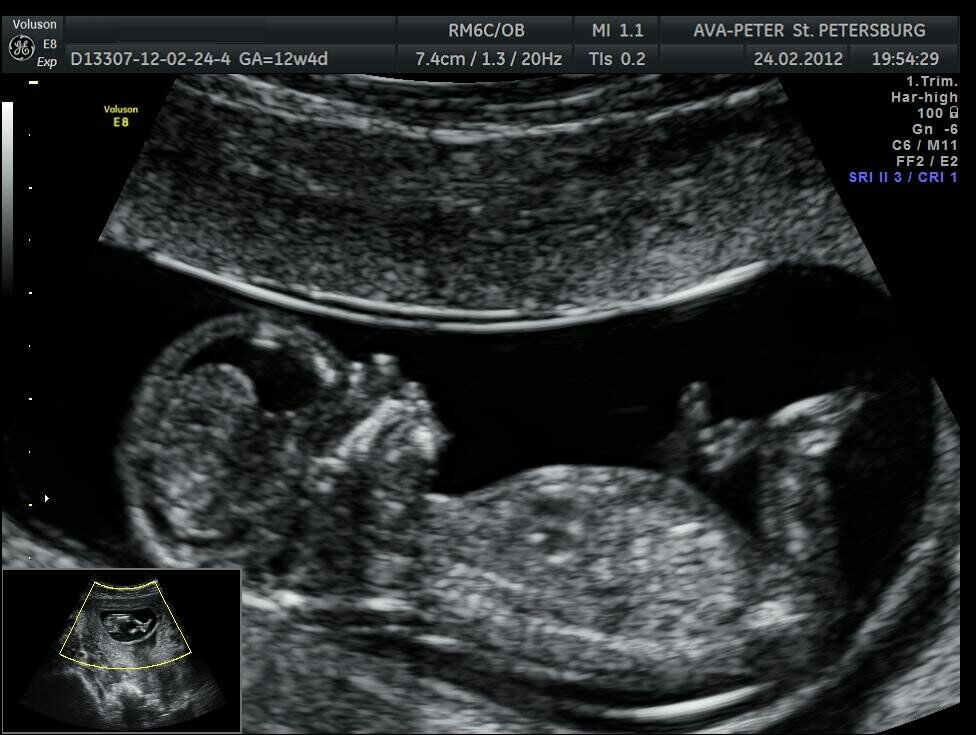

Так выглядит малыш на стадии развития 19-21 неделя. рост около 19 см, а вес 350 грамм.

Кстати, забыла сказать, как-то смотрела телепередачу "беременна в 16" и у девчонки подозревали патологию плода, потому что ТВП (толщина воротникового пространства) была увеличина, сейчас в кратце что это такое:

ТВП толщина воротникового пространства от 1.6 мм до 1.7 мм. Один из самых важных параметров, говорит о наличии хромосомных нарушений у плода. При патологии ТВП достигает 3 мм.